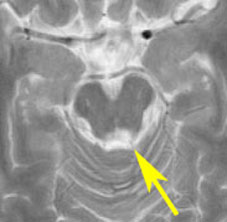

17歳で滑車神経麻痺で発症した例